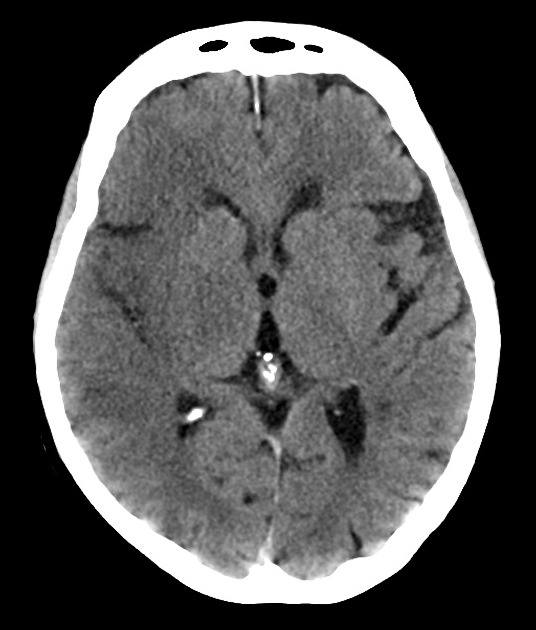

Nhồi máu não

» Thông tin: Nam giới – 60 tuổi.

» Lâm sàng: Đau đầu + Liệt nửa người trái / NIHSS 18 điểm.

# Nhồi máu sớm bán cầu phải thuộc vùng cấp máu ĐM não giữa / Huyết khối ĐM não giữa phải.